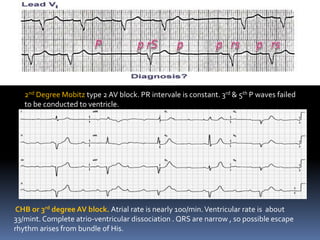

2nd Degree Mobitz type 2 AV block. PR intervale is constant. 3rd & 5th P waves failed

to be conducted to ventricle.

CHB or 3rd degree AV block. Atrial rate is nearly 100/min.Ventricular rate is about

33/mint. Complete atrio-ventricular dissociation . QRS are narrow , so possible escape

rhythm arises from bundle of His.

2nd Degree Mobitztype 2 AV block. PR intervale is constant. 3rd & 5th P waves failed to be conducted to ventricle. CHB or 3rd degree AV block. Atrial rate is nearly 100/min.Ventricular rate is about 33/mint. Complete atrio-ventricular dissociation . QRS are narrow , so possible escape rhythm arises from bundle of His.